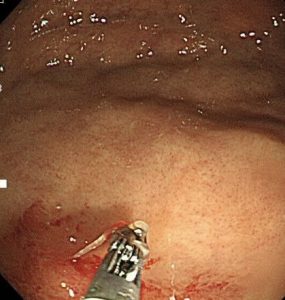

胃の粘膜に、アニサキス虫体が頭を突っ込んで食いついています。

アニサキス虫体はとぐろを巻いています。

周りの粘膜は、炎症を起こして真っ赤になっています。痛々しいですね。

「鉗子」という虫体を除去する器具が、内視鏡スコープから出てきました。

頭が胃粘膜内に残ってしまわないように、アニサキス虫体を慎重に引き抜いていきます。